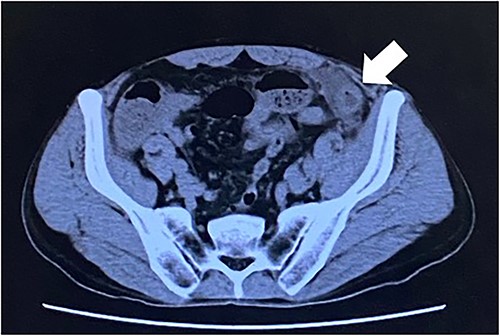

Computed tomography revealed caliber changes in the small bowel at the site of post-hernia repair in the left inguinal region (Figs 1 and 2), and the patient underwent laparoscopic surgery under general anesthesia. Intraperitoneal observation revealed that the peritoneal suture in the left inguinal region was detached, and a hole in the peritoneum had formed a hernial orifice (Fig. 4), causing SBO because of preperitoneal herniation (Fig. 3). The hernia was released, the peritoneal hole was sutured again and the surgery was completed. The postoperative course was good, and the patient was discharged from the hospital on the third postoperative day after reoperation.

The white arrow shows the site of caliber change in the small bowel (axial section image).